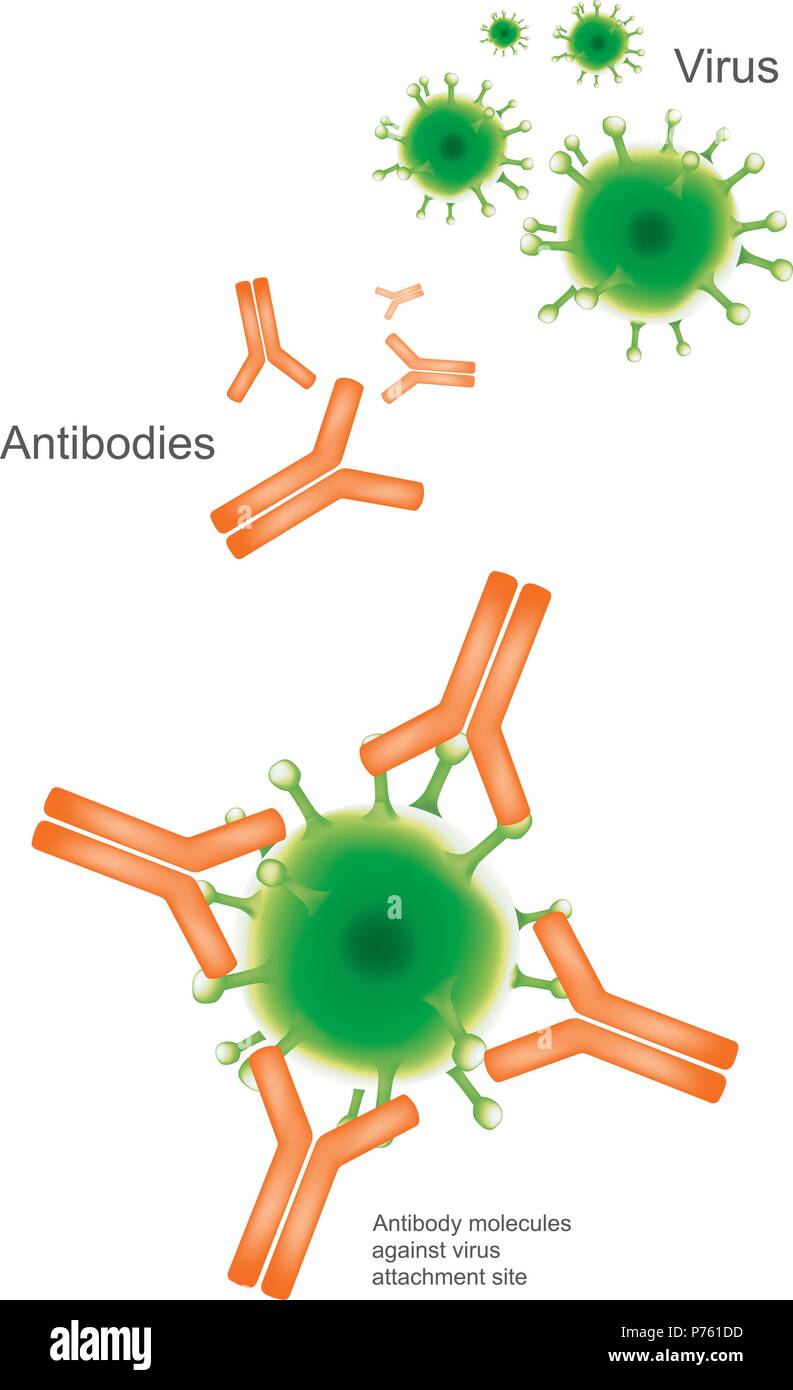

Anticorpo e virus. Illustrazione medico e sanitario ed infografico. Illustrazione Vettorialehttps://www.alamy.it/image-license-details/?v=1https://www.alamy.it/anticorpo-e-virus-illustrazione-medico-e-sanitario-ed-infografico-image210959881.html

Anticorpo e virus. Illustrazione medico e sanitario ed infografico. Illustrazione Vettorialehttps://www.alamy.it/image-license-details/?v=1https://www.alamy.it/anticorpo-e-virus-illustrazione-medico-e-sanitario-ed-infografico-image210959881.htmlRFP761DD–Anticorpo e virus. Illustrazione medico e sanitario ed infografico.

Un anticorpo (Ab), noto anche come una immunoglobulina è una grande a forma di Y proteina prodotta principalmente da cellule di plasma che viene utilizzata dal sistema immunitario Illustrazione Vettorialehttps://www.alamy.it/image-license-details/?v=1https://www.alamy.it/foto-immagine-un-anticorpo-ab-noto-anche-come-una-immunoglobulina-e-una-grande-a-forma-di-y-proteina-prodotta-principalmente-da-cellule-di-plasma-che-viene-utilizzata-dal-sistema-immunitario-135199938.html

Un anticorpo (Ab), noto anche come una immunoglobulina è una grande a forma di Y proteina prodotta principalmente da cellule di plasma che viene utilizzata dal sistema immunitario Illustrazione Vettorialehttps://www.alamy.it/image-license-details/?v=1https://www.alamy.it/foto-immagine-un-anticorpo-ab-noto-anche-come-una-immunoglobulina-e-una-grande-a-forma-di-y-proteina-prodotta-principalmente-da-cellule-di-plasma-che-viene-utilizzata-dal-sistema-immunitario-135199938.htmlRFHRXTW6–Un anticorpo (Ab), noto anche come una immunoglobulina è una grande a forma di Y proteina prodotta principalmente da cellule di plasma che viene utilizzata dal sistema immunitario